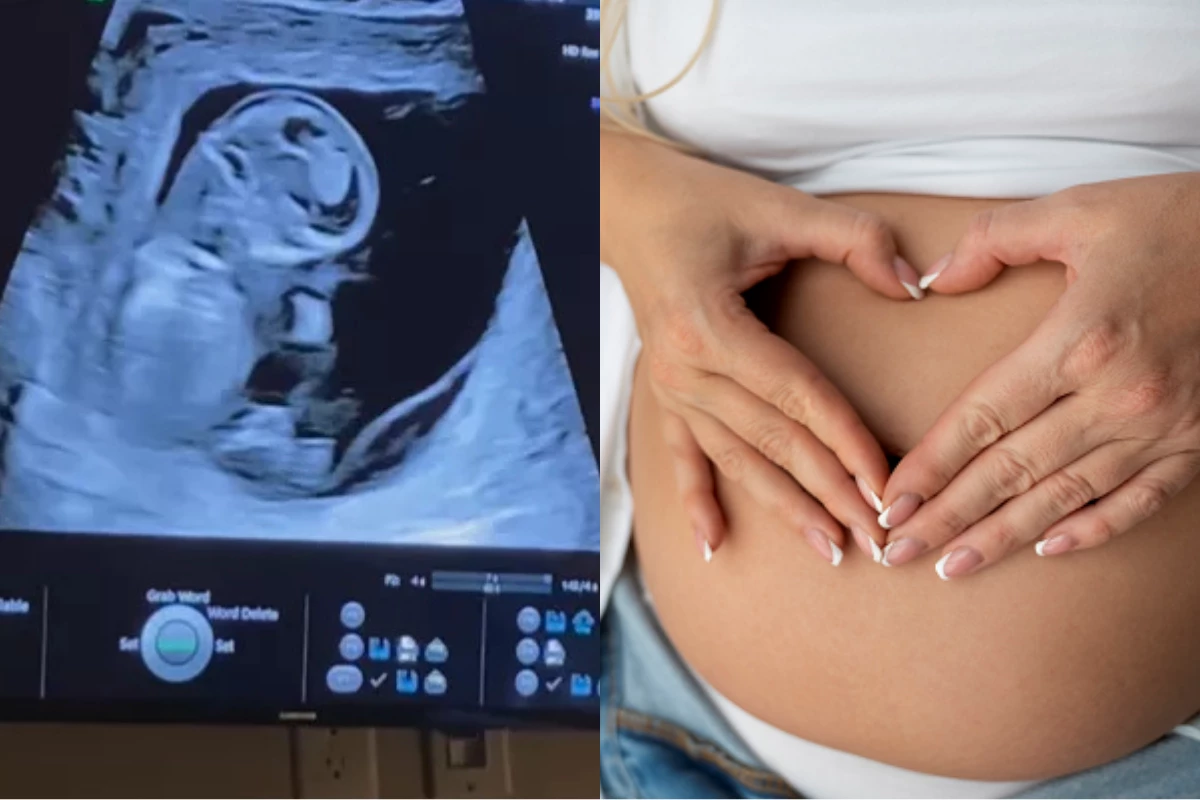

Pais escolhem o amor diante da perda anunciada: Joshy viveu no ventre e no coração

Casal decidiu criar memórias durante a gestação de filho com Trissomia 18, uma condição genética incompatível com a vida.